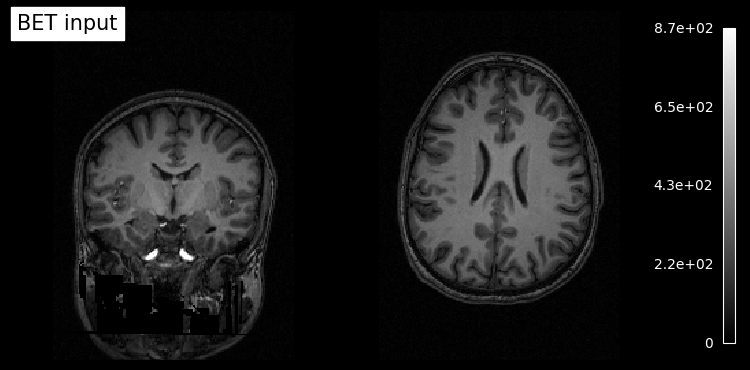

# Plot original input file

plotting.plot_anat(input_file, title='BET input', cut_coords=(10,10,10),

display_mode='ortho', dim=-1, draw_cross=False, annotate=False);

# Plot skullstripped output file (out_file) through the outputs property

plotting.plot_anat(res.outputs.out_file, title='BET output', cut_coords=(10,10,10),